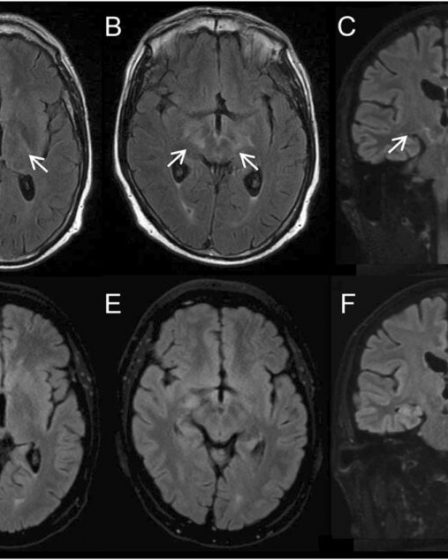

Napredno slikanje kaže, da je možganska megla, povezana z lajmsko boreliozo, resnična

Nancy Dougherty, Raziskovalni center za boreliozo, Johns Hopkins Medicine https://www.lymedisease.org/lyme-related-brain-fog-is-real/ V ZDA zboli vsako leto za lajmsko boreliozo približno 476.000 ljudi. Ocenjuje se, da od teh 10–20 % trpi za težjimi simptomi, ki presegajo akutno fazo okužbe. Vztrajni simptomi vključujejo hudo utrujenost, bolečino in kognitivne težave. Na žalost je te simptome težko potrditi s trenutnimi …